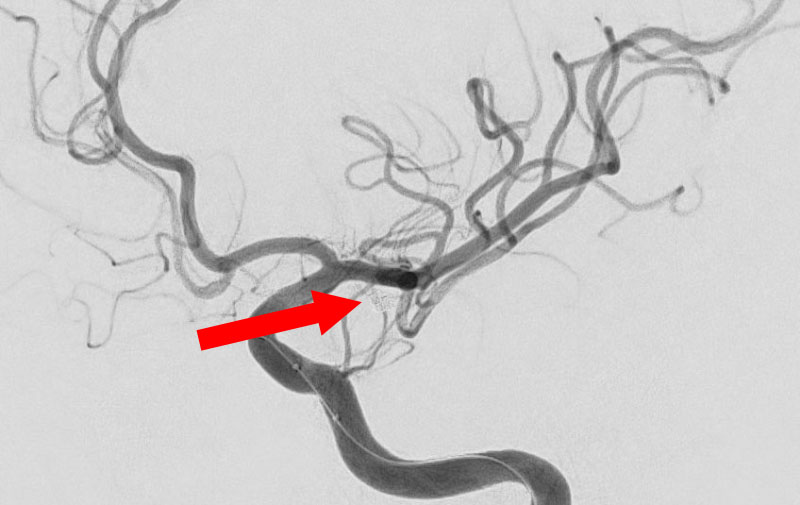

くも膜下出血

左中大脳動脈瘤破裂

40代

救急外来

No.1596 手術前

No.1596 手術中

No.1596 手術後